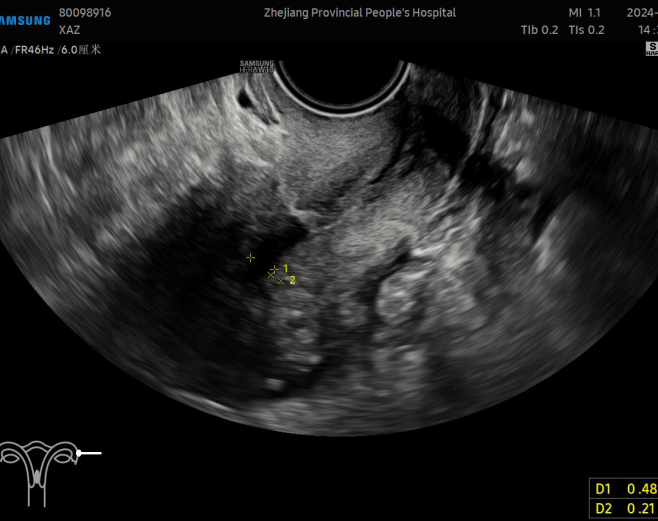

地屈孕酮20mg qd po每次月经第5天开始口服;术后第3个月:月经量少,无痛经,无明显副反应。复查阴道B超:子宫前位,切面大小正常,后壁肌层回声增粗,分布不均匀,内见多个条状回声,前峡部见0.9cm*0.7cm*0.9cm(宽径*长径*深径)无回声区。单层内膜厚度0.2cm,回声均匀,宫腔分离约0.5cm。提示:子宫后壁肌层回声改变,考虑术后改变;子宫前峡部暗区,憩室可能。CA125:14.1U/ml。阴道超声图如下: